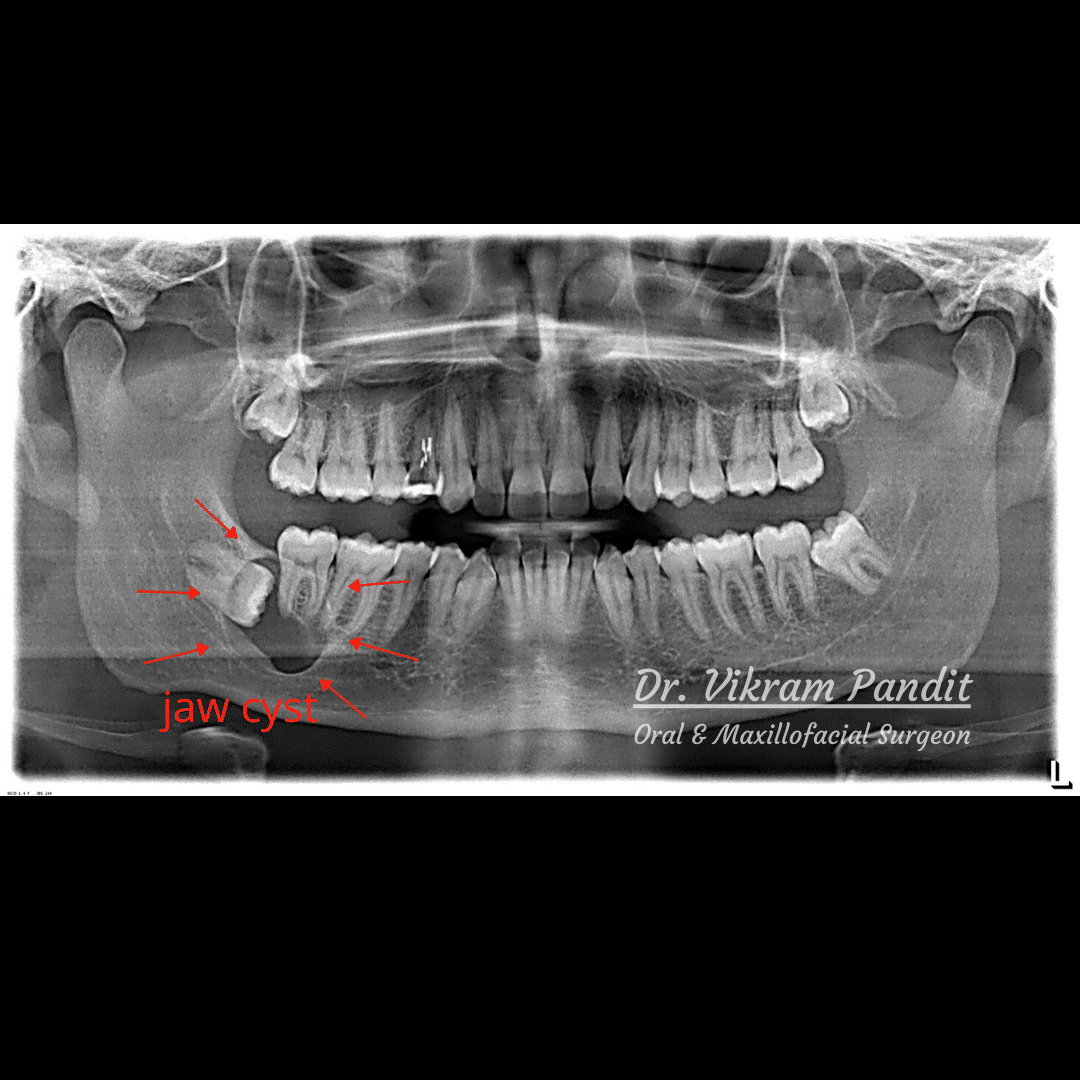

Jaw Cyst/Tumour Surgery and Treatments at Pandit Clinic in Pune Jaw Cyst X Ray Cystic should not be confused with lytic as solid radiolucent lesions can also appear lytic (see: What are the symptoms of a cyst or tumor in my jaw? An odontogenic cyst associated with the apex of a tooth with a crown, thus a diseased tooth, is consistent with a periapical radicular cyst. Most cysts or tumors that develop in your. Jaw Cyst X Ray.

Jaw Cyst Removal In Pune By Expert Surgeon Dr. Vikram Pandit Jaw Cyst X Ray A series of 3d images that show the. A single image that shows your teeth, upper jaw and lower jaw. An odontogenic cyst associated with the apex of a tooth with a crown, thus a diseased tooth, is consistent with a periapical radicular cyst. What are the common types of. Radiolucent lesions of the jaw). Most cysts or tumors that. Jaw Cyst X Ray.